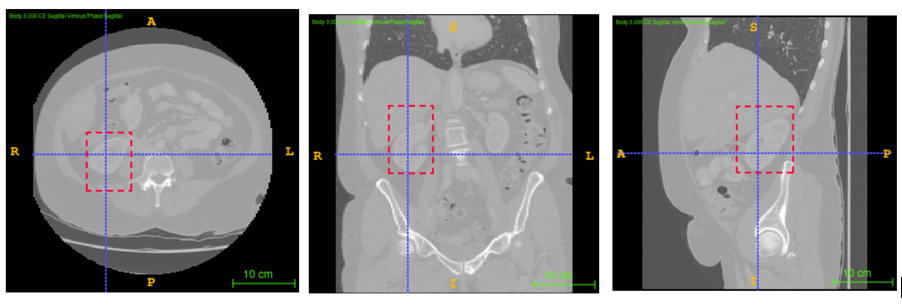

3.2.2 Annotation

The annotation process using ITK-SNAP in the three planes is illustrated in Fig 1 for creating a 3D bounding box around a lumbar spine region. The annotations of spleen, left and right kidneys are illustrated by Figures 2, 3 and 4 respectively.

The dataset was provided by the Prince of Wales Hospital, Randwick, NSW, Australia in an anonymised form after ethics approval (refer 3.1), and included 110 abdomen CT scans with a slice thickness of 3mm for lumbar spine and left kidney and 104 scans for spleen and right kidney localisation. The data set was manually annotated and verified by a radiologist with 10 years of experience, to identify the two diagonally opposite corner points of a 3D bounding box around the ROI. Annotations were performed to localise left and right kidneys using ITK-SNAP as described in section 3.2.2.